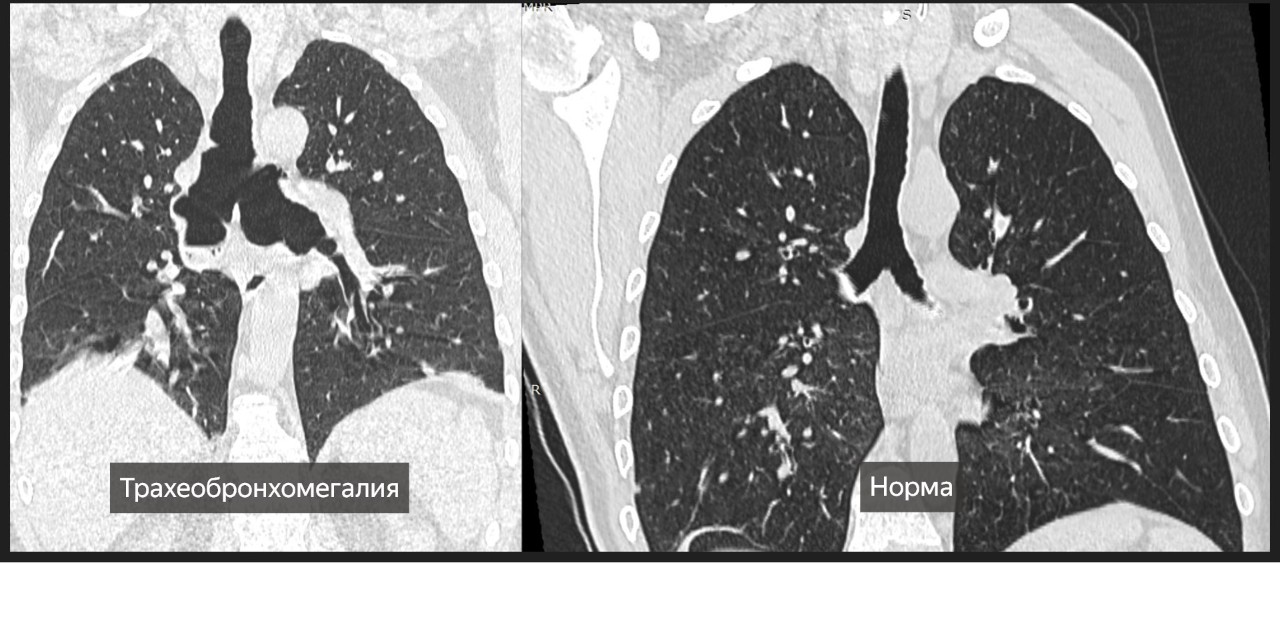

На КТ грудной клетки выявлены: ателектаз, скопление секрета в бронхах и трахеобронхомегалия — ключевой признак синдрома Мунье–Куна. Такое расширение трахеи и крупных бронхов делает пациента уязвимым к частым инфекциям дыхательных путей.